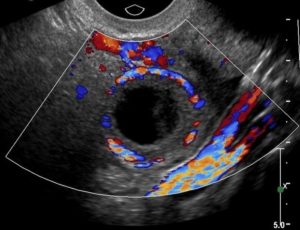

Анэхогенный объект в этом органе говорит о наличии кисты.

Они бывают такими:

- фолликулярными – с плотной структурой и четкими границами;

- эндометриоидными – с твердой капсулой, с неоднородным содержимым;

- серозными (часто это может быть проявлением более серьезного заболевания).Серозная цистаденома яичника на УЗИ